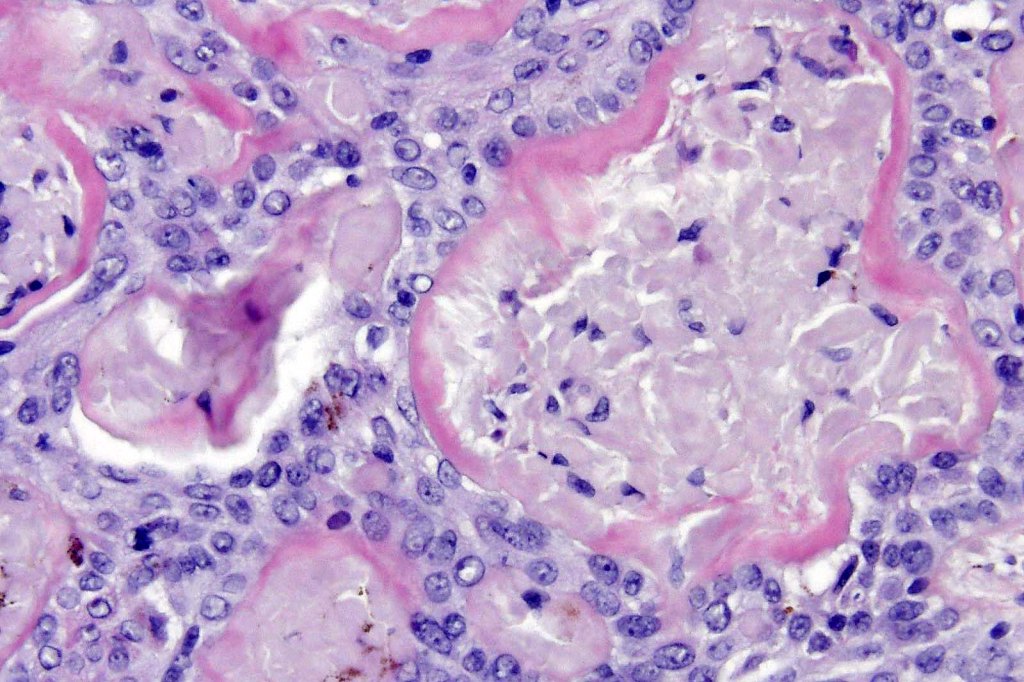

•Anastomosing basaloid, narrow epithelial strands associated with a prominent fibrous (sometimes myxoid) stroma

•Peripheral palisade

•Round to oval vesicular nuclei with small nucleoli

•Retraction artifact variably present